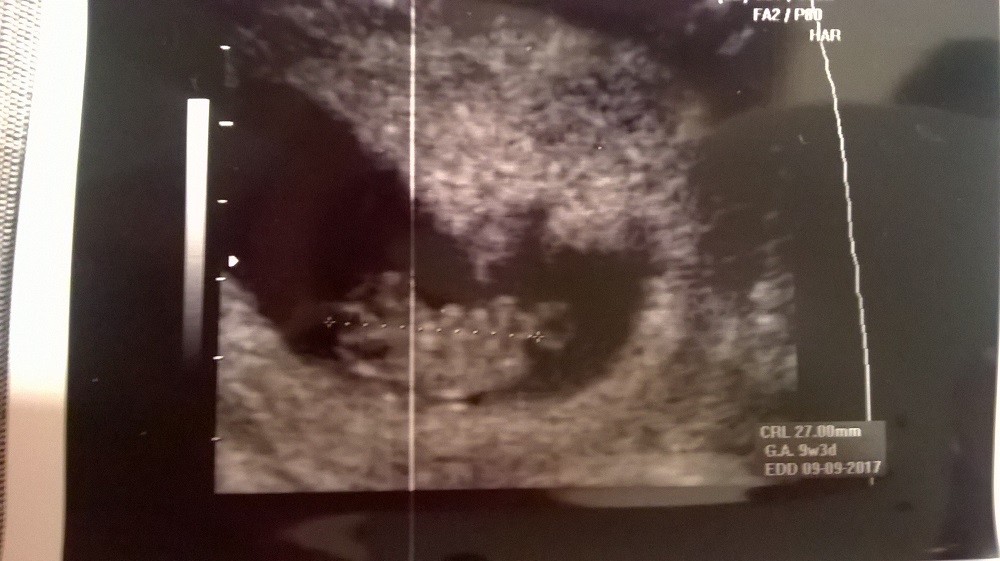

Moje dzidki zdrowe ...:)

WP_20170207_013.jpg

• WP_20170207_013.jpg

171,4 KB · Wyświetleń: 702